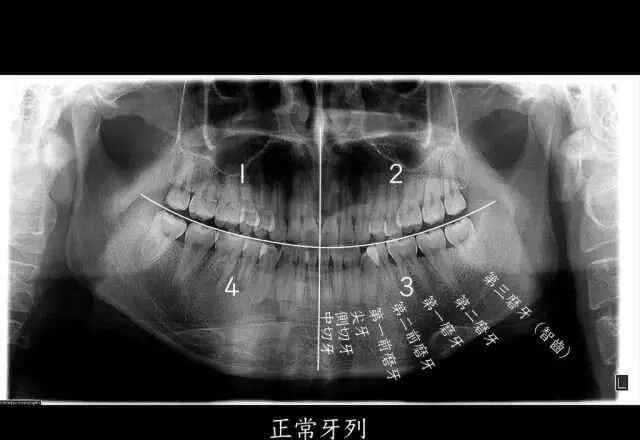

智齒,也就是第三磨牙,位於(yu) 口腔最遠最深的位置。圖源:作者

如果我們(men) 把一個(ge) 正常成年人的口腔分為(wei) 左上、左下、右上、右下四個(ge) 區域的話,每個(ge) 區域會(hui) 有 8 個(ge) 牙齒,長在最後的第8顆牙齒,就是我們(men) 口中的“智齒”,也是我們(men) 的第三磨牙。